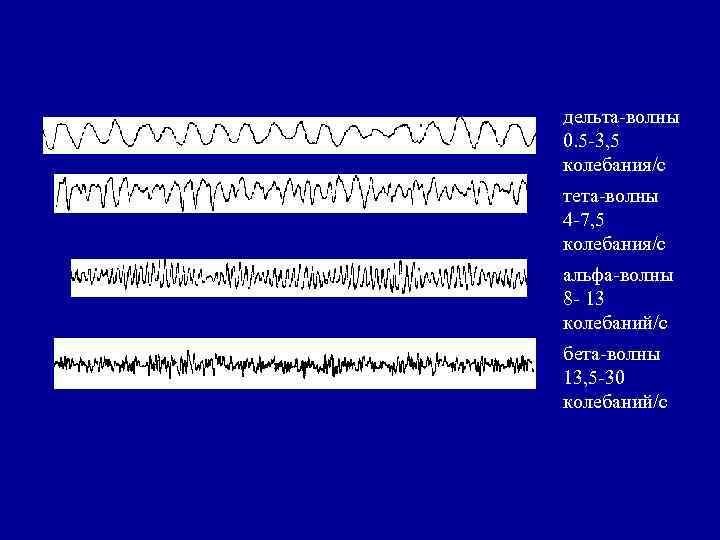

дельта-волны 0. 5 -3, 5 колебания/с тета-волны 4 -7, 5 колебания/с альфа-волны 8 - 13 колебаний/с бета-волны 13, 5 -30 колебаний/с

дельта-волны 0. 5 -3, 5 колебания/с тета-волны 4 -7, 5 колебания/с альфа-волны 8 - 13 колебаний/с бета-волны 13, 5 -30 колебаний/с